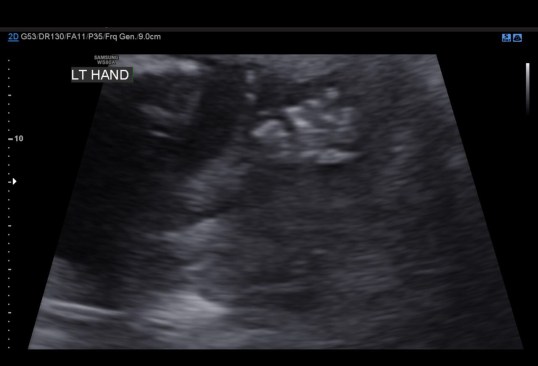

I seriously do not know where time is going, but it seems that after Kenley died the end of the year zooms by. Once Landon starts school again, everything just goes super fast. So yesterday was my anatomy scan. I was 18+5, and everything looked great. She was being stubborn though so we have to go back on November 16th for another ultrasound (obviously not complaining). We got to see her little face for a few seconds; the look like skeletons right now, but it was still cute. She also proved to us that she was indeed a female. She showed us her hands and feet, and also her cute little belly.